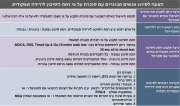

| 14:39, 14 בספטמבר 2023 | טבלה 4 ספר סוכרת - סוכרת היריון.png (קובץ) |  |

161 קילו־בייטים | Roeitul | 1 | |

| 14:37, 14 בספטמבר 2023 | טבלה 4.png (קובץ) |  |

28 קילו־בייטים | Roeitul | 1 | |

| 11:51, 14 בספטמבר 2023 | טבלה 2. הצעה לבדיקות הסקר.png (קובץ) |  |

1.25 מגה־בייטים | Roeitul | 1 | |

| 11:48, 14 בספטמבר 2023 | טבלה 2. הצעה לבדיקות הסקר והניטור במהלך ההיריון.jpg (קובץ) |  |

160 קילו־בייטים | Roeitul | 1 | |